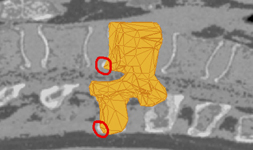

Das Modell wird seine Form im Verlauf des Segmentierungsprozesses der des Wirbels im Volumen annähern. Es wird zunächst durch Extraktion aus dem Datensatz einer Wirbelsäule generiert und anschließend in eine allgemeine Form gebracht. Man erhält ein Oberflächenmesh, welches zur Stabilisierung in ein tetraedisiertes Modell überführt wird. Es wird durch ein Partikelsystem, bestehend aus einer Menge masseloser Punkte und verbindener Federn repräsentiert, wodurch das System als physikalisch basiert bezeichnet werden kann. Die Deformation erfolgt mittels Relaxation, eines statischen Systems, um einen realistischen und interaktiven Segmentierungsvorgang zu gewährleisten.

Das Modell wird in seiner initialen und verkleinerten Form im Volumen, innerhalb des zu segmentierenden Bereichs platziert. Zusätzliche Sensoren an den Kontrollpunkten des Modells reagieren auf Volumenwerte. Durch Auswertung von Intensitäten und Gradienten der einzelnen Voxel steuern sie die Deformation des Systems und bewegen die Punkte des Modells an die entsprechenden Positionen im Volumen. Das Modell wird dabei zunächst gedehnt, und ein zusätzlicher Skalierungsschritt sorgt für eine optimale Größenanpassung. Deformation und die optionale Skalierung wiederholen sich iterativ, bis das Modell das Zielobjekt detektiert hat und der Segmentierungsvorgang beendet ist.